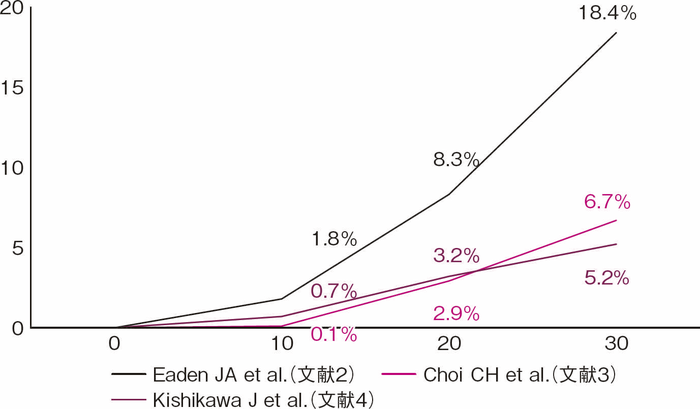

UCは長期罹患に伴う粘膜の慢性炎症を背景に発癌リスクが上がることが知られており,1925年にCrohnとRosenbergが最初のUC関連大腸癌の報告を行って以降,これまで多くの報告がなされてきた1)。UC関連大腸癌は罹患年数が長くなるにつれ発生リスクが上がるとされ,2001年Eadenらの報告では,浸潤癌の累積発生率は10年で1.8%,20年で8.3%,30年で18.4%であることが示された2)。一方近年では,英国Choiらの報告にて10年で0.1%,20年で2.9%,30年で6.7%とされ,罹患年数に伴う累積発生率は低い値を示している3)(図1)。本邦ではKishikawaらの報告によると,浸潤癌の累積発生率は10年で0.7%,20年で3.2%,30年で5.2%でありChoiらの結果同様であったが,一方でdysplasiaも含めた腫瘍性病変の累積発生率は10年で3.3%,20年で12.1%,30年で21.8%であり,依然長期経過での発生率は高く注意すべき問題である4)(図2)。また炎症の範囲が広いほど発癌リスクが上がることも知られており,Ekbomらの報告によると一般集団と比較した大腸癌発生の相対危険度は,直腸炎型では1.7倍,左側大腸炎型では2.8倍,全大腸炎型では14.8倍であり,広範囲の炎症を伴う場合にも注意を要する5)。

図1 大腸浸潤癌累積発生率